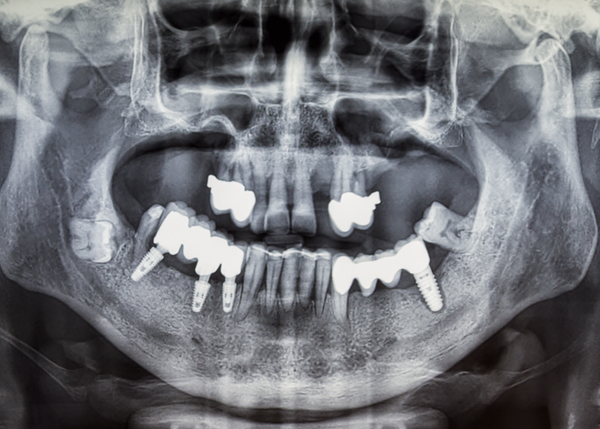

디지털 정밀 진단

일반 임플란트

치아 상태 및 신경의 위치를 2D(평면)으로만 확인이 가능해

정확한 진단이 어려움

3D CT를 통한 컴퓨터 분석

현재 턱 뼈와 잇몸의 상태를 3차원 입체 영상으로 확인이 가능해

정밀 진단에 따른 오차 없는 수술이 가능